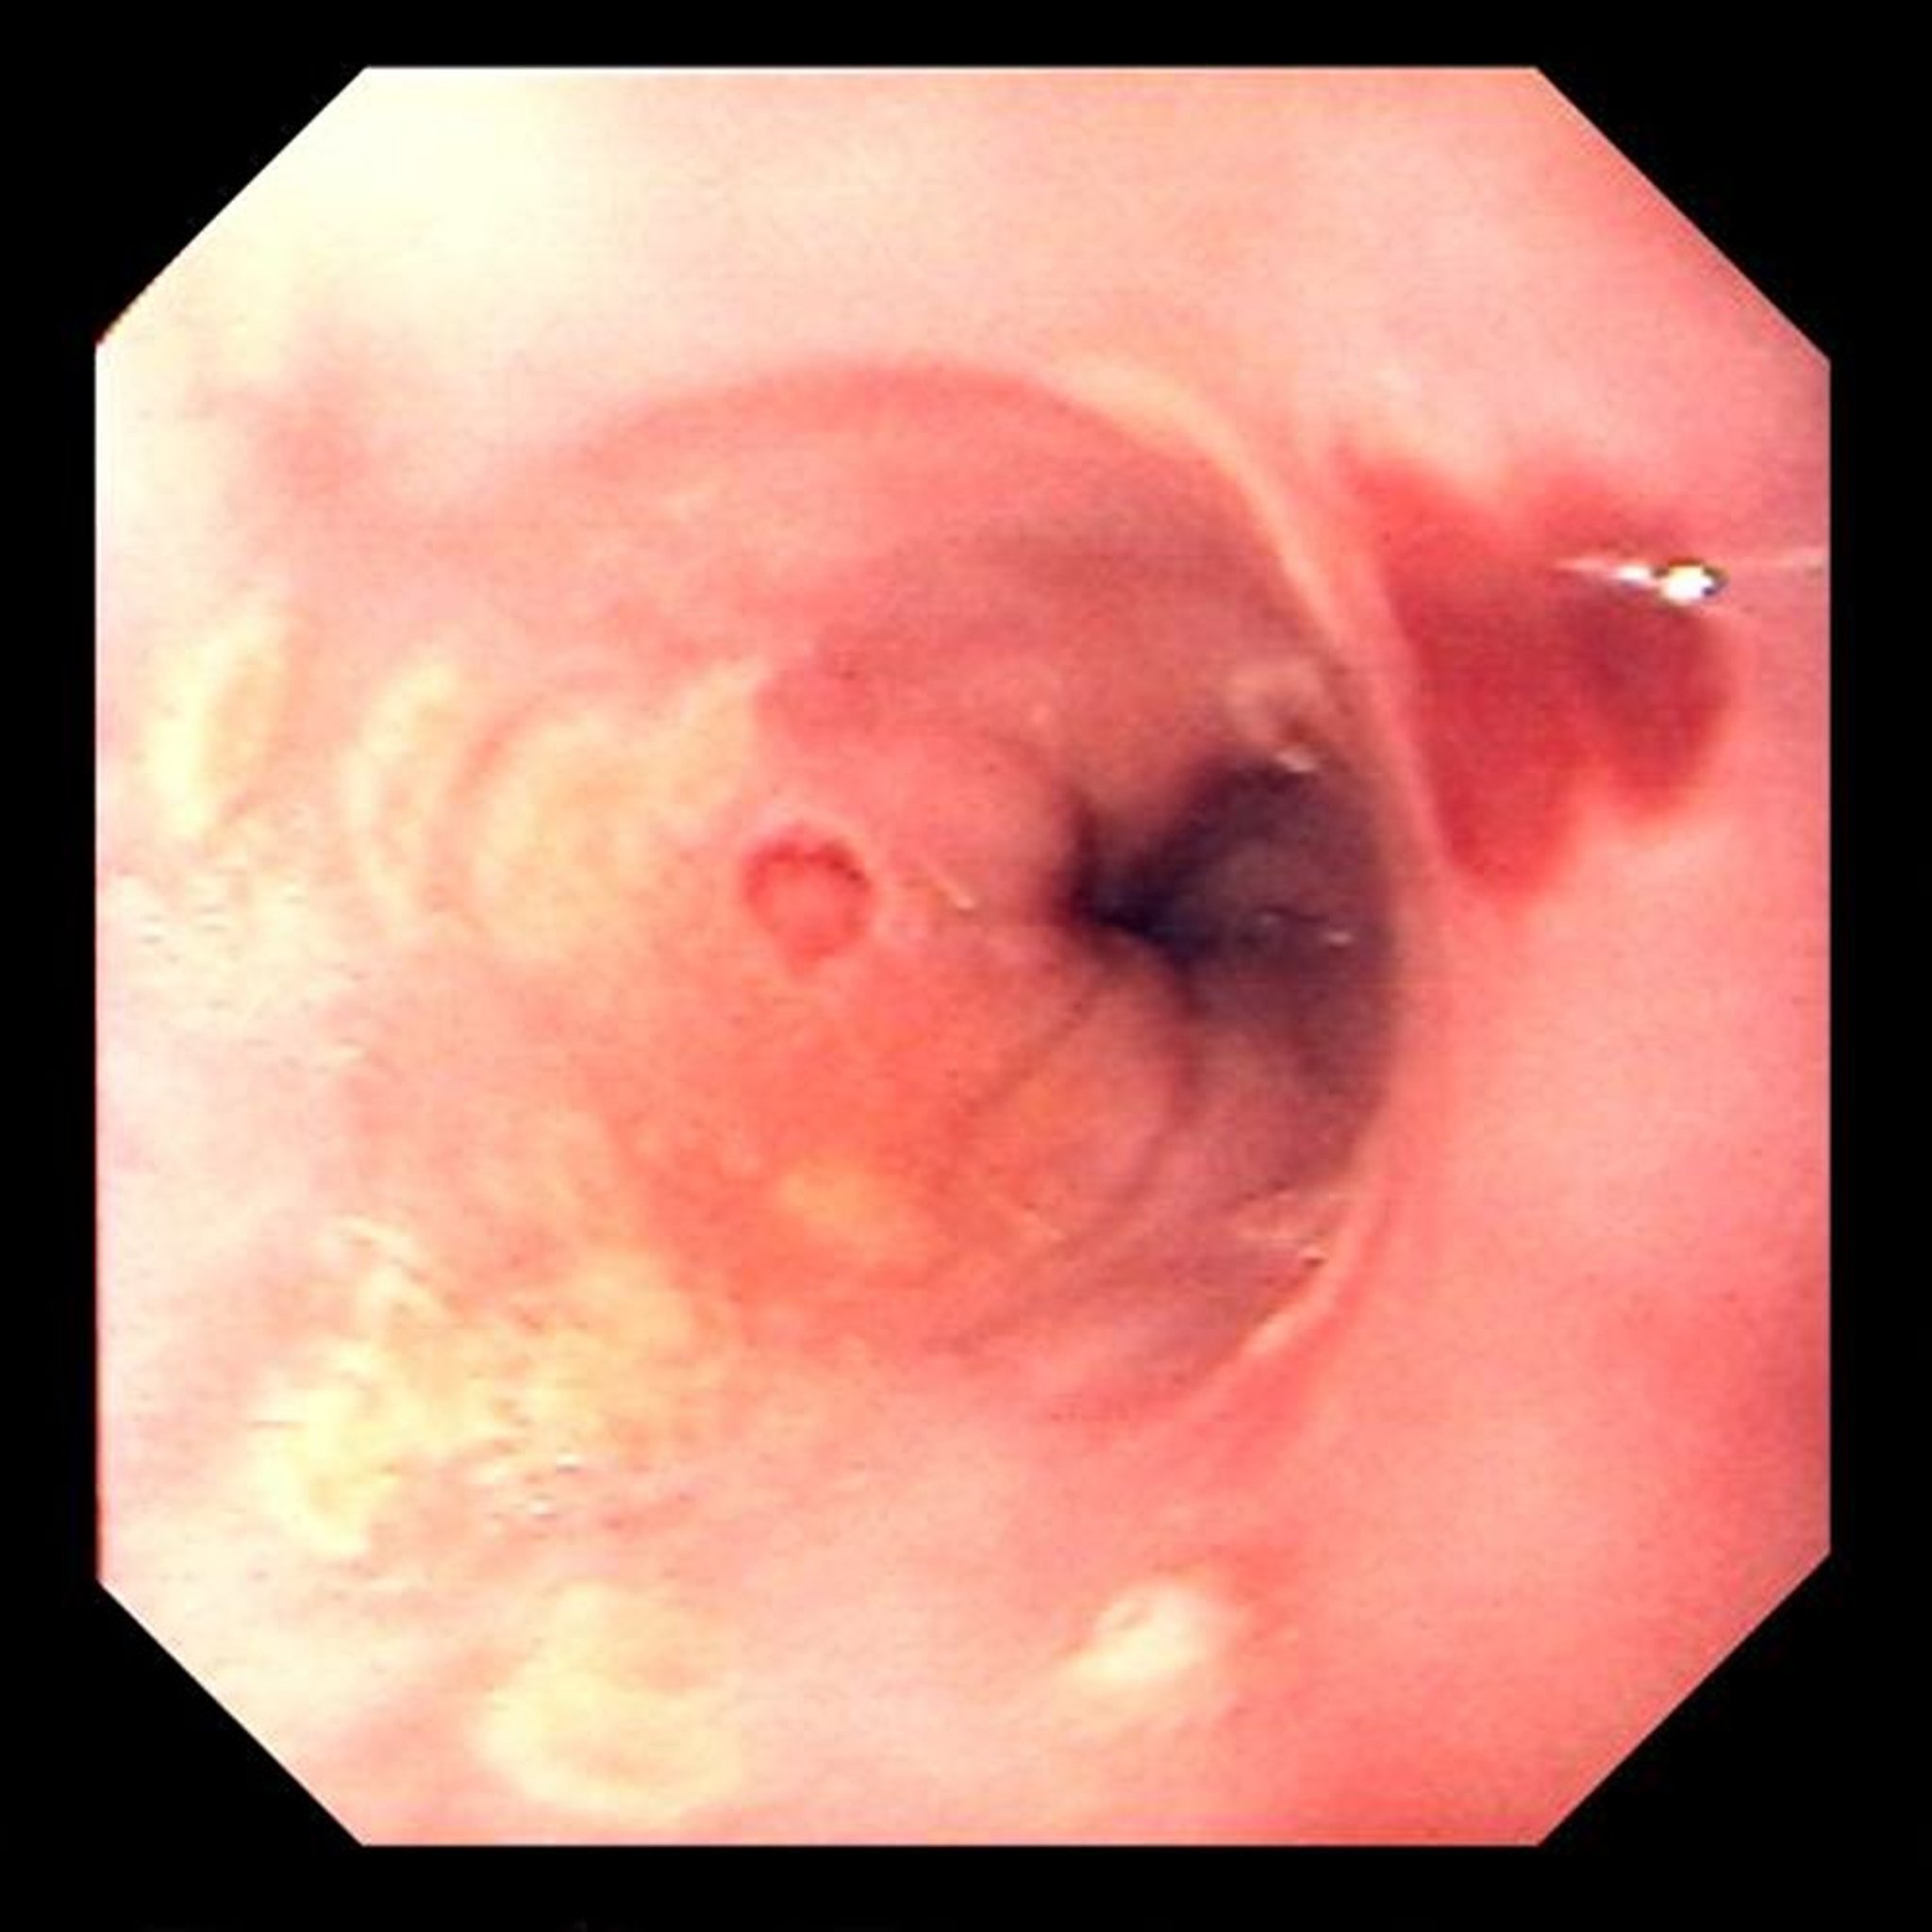

Эзофагит, вызванный вирусом простого герпеса

Фокальные изъязвления характерны для эзофагита, вызванного вирусом простого герпеса.

Image provided by David M. Martin, MD.